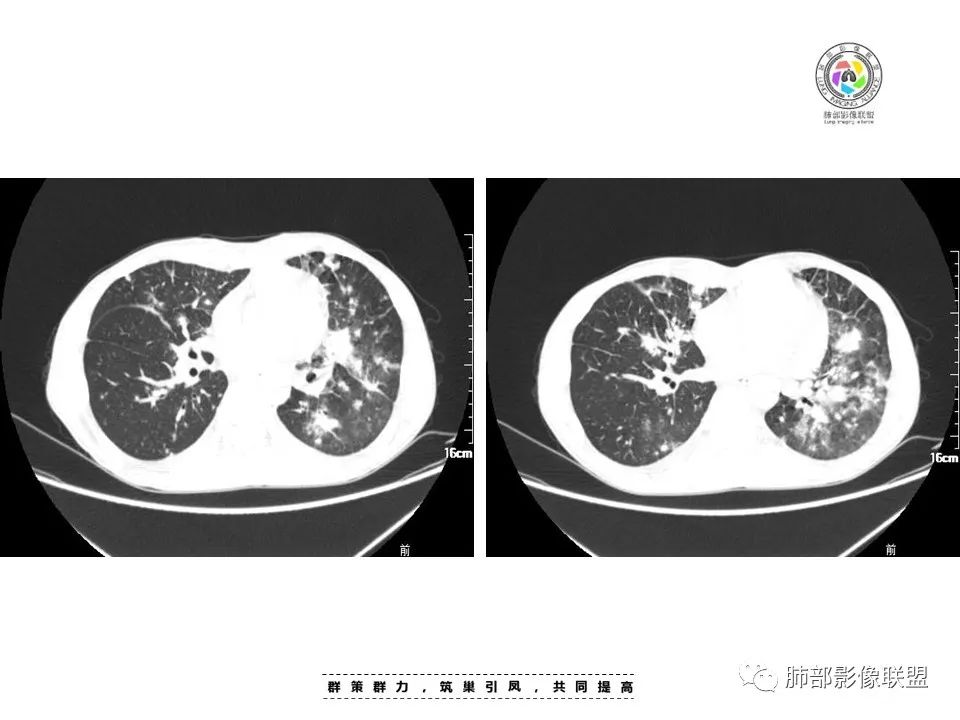

周一晚读病例:男性45岁,发热、纳差,全身散在暗紫色皮疹,结合CD4,符合HIV;肺部影像表现:两肺散在实性结节及磨玻璃密度影,实性结节伴晕征,部分沿支气管血管束分布,支气管血管束增粗,以两肺下叶为著,类似火焰征,双侧胸腔少量积液;首先考虑卡波西肉瘤,鉴别淋巴瘤增值性病变,淋巴瘤样肉芽肿/淋巴瘤,最后挂上马尔尼菲青霉菌病。

中年男性,发热、全身散在暗紫色丘疹,查CD4+T细胞64个/ul,临床信息提示AIDS并发卡波西肉瘤;CT提示双肺多发实性结节影及毛玻璃结节,部分呈点晕征,右上肺大姐姐边缘膨隆、分叶伴晕;双下肺结节沿支气管血管束分布,中轴间质增粗,部分支气管堵塞,叶间裂结节状增厚,部分结节胸膜下分布,可疑局部小叶间隔增厚,肺部病变呈淋巴分布特点,结合临床肺部病变考虑肺卡波西肉瘤,鉴别淋巴瘤。

两肺弥漫性性结节状、小片状及片状带晕的病灶,煎蛋征、点晕征,主要分布两肺中下叶,病灶周围小叶间隔增厚呈网格状影,部分病灶累及胸膜,伴两侧胸膜增厚。

2.本例双肺小叶间隔增厚明显,多发结节影及片状实性密度影,沿血管支气管束分布为主,两侧较为对称,病灶多环以磨玻璃晕,边界不清。

双侧胸腔少量积液。双肺门及纵隔未见明确肿大淋巴结,纵隔结构间隙模糊。

1.结节型:两肺沿支气管血管束分布的结节影,呈火焰状或星芒状、挂果征,局部周围出血磨玻璃影(肺泡出血或水肿)。

斑片渗出影,部分融合呈“火焰样”,同时有火焰样结节,小叶间隔增厚等表现。

还可以有纵隔及腋下淋巴结增大,胸腔积液等表现。